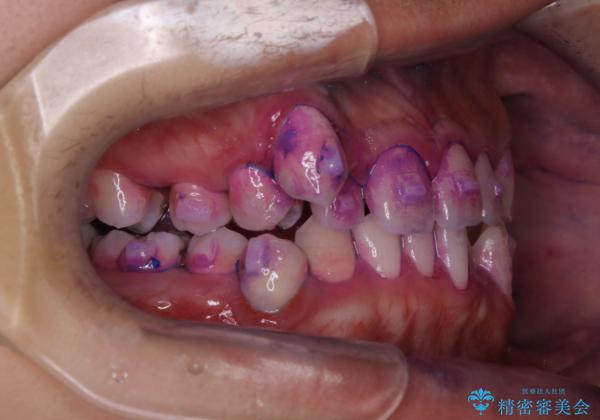

しかし、プラークは歯の色と似ているため、見ただけでは付着しているかどうかがハッキリとは分かりません。

染め出し液を使ってプラークを染め出すことにより、普段の歯みがきで磨き残している場所を目で確かめることができます。

日々の歯磨きを上達するには、まずどこが磨けていないか認識することが大切です。